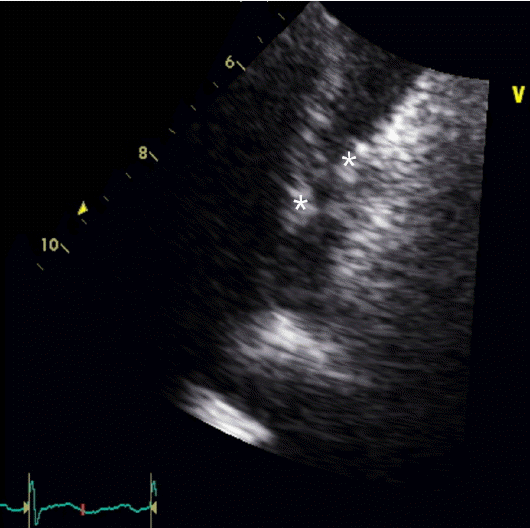

Figure 1.

Chest CT showed deep vein thrombosis on admission and after discharge: Multiple peripheral nodular lesions and peribronchial patchy consolidations with ground glass opacities are seen on both lobes on admission day 6 (A). Both lower lobar pulmonary arteries show massive thromboembolism (arrow) (B) and the follow-up CT angiography shows improvement (D). Parenchymal pulmonary infiltrations also show improvement in the follow-up CT after discharge (C).

환 자: 32세, 여자주 소: 3주간 지속되는 발열현병력: 내원 6주 전 파라콰트 종류인 그라목손(gramoxone) 음독으로 타병원 응급실에 입원하여 위 세척 및 대퇴정맥 이중내강 카테터를 통한 응급 혈액투석을 시행하였다. 그라목손으로 인한 폐 섬유증을 예방하기 위해 prednisolone 1 mg/kg 1일 1회 및 cyclophosphamide 충격요법을 하였으며 치료 시작 2일 후부터 경구 prednisolone 50 mg 1일 1회 요법으로 바꾸어 복용하였다. 환자는 그라목손 음독으로 인하여 구강 궤양이 발생하였으며 경구 섭취가 힘들어 우측 쇄골하정맥 카테터를 삽입하여 완전 정맥 영양을 시행하였다. 입원 21일째부터 발열이 동반되어 시행한 혈액배양 검사에서 Candida tropicalis가 배양되어 입원 25일째에 중심정맥 카테터를 제거하고, 경구 prednisolone 25 mg/day로 감량하면서 fluconazole 800 mg 부하용량 정맥주사 투여 후 400 mg 24시간 간격으로 정맥주사하기 시작하였다.입원 29일째 단순 흉부 방사선 사진에서 우측 하엽에 폐렴 소견이 확인되어 원내 획득 폐렴 가능성을 고려하여 항생제 치료를 시작하였고 입원 36일째에는 경구용 스테로이드 복용도 중지하였다. 그러나 여전히 Candida tropicalis에 의한 진균혈증과 39도 이상의 발열이 지속되고 이전에 없던 호흡곤란을 호소하여 입원 36일째 fluconazole은 중지하고 amphotericin B 1 mg/kg 24시간마다 정맥주사로 변경 후 입원 37일(진균혈증 발생 16일)에 본원 응급실로 전원되었다.과거력: 약물 남용의 과거력은 없었으며, 심내막염 등의 병력도 없었다.개인력: 흡연력, 음주력은 없었다.신체 검사: 활력 징후는 혈압 140/89 mmHg, 맥박수 120회/분, 호흡수 19회/분, 체온 39℃이었으며 의식도 명료하였다. 만성 병색을 나타내고, 폐 양측 하엽에서 수포음이 청진되었으며 심음은 규칙적이고 잡음이 청진되지 않았다. 좌안의 시력 저하를 호소하였으며 다른 신경학적 증상은 보이지 않았다. 양측 상 하지에 연부조직 감염을 의심할만한 소견도 보이지 않았다.검사실 소견: 말초혈액검사에서는 백혈구 8,020/mm3(호중구 79.5%, 림프구 13.1%), 혈색소 8.3 g/dL, 혈소판 231,000 /mm3으로 호중구 비율 증가 및 빈혈이 있었다. 적혈구 침강 속도 63 mm/hr, C-반응단백 26.94 mg/dL로 증가되어 있었다. AST/ALT 44/60 U/L으로 약간 상승되어 있었고, 알부민 2.5 g/dL로 감소하였으며, 신기능은 정상이었다. 고배율 시야 소변 검사에서 현미경적 혈뇨를 동반하였으며 그 외 검사에서는 특이 소견이 없었다. 진균혈증 발생경과 17일에 시행한 말초 혈액배양 검사 3쌍은 모두 음성이었고 이후 시행한 모든 말초 혈액배양 검사도 배양 음성이었다.방사선 소견: 단순 흉부 방사선 사진에서 폐 양측 하엽에 반점형 침윤(patchy infiltration) 폐렴 소견이 보였다. 입원 2일(진균혈증 발생 18일)째 장기간 진균혈증을 보인 것에 대하여 흔한 합병증인 심내막염 발생을 확인하기 위해 경흉부 심장초음파 검사를 시행하였으며 좌심실 수축기 기능이나 심근벽운동 장애는 없었고 심내 증식증도 없었다.입원 6일(진균혈증 발생 22일)째까지도 39℃ 이상 열이 지속되어 흉부, 복부 컴퓨터단층촬영술(CT)을 시행하였다. 흉부 CT에서 양측 폐야에 다발성 결절 음영이 있고 기관지 주위 반점형 경화성 병변(peribronchial patchy consolidation) 및 젖빛유리혼탁(ground glass opacity), 간질비후(interstitial thickening)가 관찰되었으며 우하분엽 폐동맥과 그 하방 및 좌하엽 폐 동맥과 그 하방으로 거의 폐 동맥의 내강 대부분을 차지하는 다발성 혈전 색전증도 관찰되었다(Fig. 1A). 입원 7일(진균혈증 발생 23일)째 경흉부 심장초음파 추적검사에서 0.1 × 1.25 cm, 0.18 × 0.82 cm의 진동하는 에코 발생 종괴(oscillating echogenic material) 2개가 우심방의 상대정맥 삽입부에서 관찰되었다(Fig. 2).폐 혈전색전증의 정확한 평가를 위해 심부 정맥 혈전 컴퓨터단층촬영(DVT-CT)을 시행하였으며 폐동맥 혈전이 우하엽 폐동맥과 그 하방 그리고 좌하엽 폐동맥과 그 하방으로 확인되었다(Fig. 1B). 입원 22일(진균혈증 발생 38일)째 추적 관찰한 DVT-CT에서는 이전과 비교하여 양측 폐에 다발성 결절 음영과 기관지 주위 경화성 병변은 일부 호전되었으며 양측 폐동맥 혈전 색전은 조금 감소하였으나 여전히 남아있었다.안과 검사 소견: 전원 당시 좌안의 시력 저하로 안과에 협진 의뢰하였고 망막의 출혈과 침윤 소견이 보여 칸디다 내인성 안내염으로 진단하였다(Fig. 3).치료 및 경과: 타병원에서 fluconazole 투여하였으나 호전보이지 않아 fluconazole 내성 고려하여 진균혈증 발생 15일부터 amphotericin B를 1 mg/kg 24시간마다 정맥주사로 투여하기 시작하였다. 전원 후에도 발작적인 호흡곤란이 지속되고 폐렴의 호전이 없으며 39도 이상 발열이 지속되어 약열의 가능성 고려하여 입원 4일(진균혈증 발생 20일)째 amphotericin B 투여를 중단하고 caspofungin 50 mg 24시간 마다 정맥주사로 변경하였다. 입원 6일째 호흡곤란과 양측 폐 동맥을 거의 다 폐쇄하는 다발성 색전으로 급성 폐 색전증에 준하여 wafarin과 enoxaparin 주사로 항응고 치료를 시작하였다. 항응고 치료와 caspofungin 총 21일 동안 치료 후 호흡곤란과 발열이 호전되며 C-반응단백도 처음 입원 당시 26.94 mg/dL에서 4.3 mg/dL까지 호전되어 환자의 경제적 부담을 고려하여 다시 amphotericin B 1 mg/kg/day로 변경하였다.Amphotericin B 25일간 총 누적용량 1,290 mg 투여 후 흉부 단층 촬영을 시행하였으며 다발성 결절 음영과 기관지 주위 반점형 경화 병변의 호전 소견 보여(Fig. 1C) fluconazole 400 mg/day 경구 투약으로 변경하였다. 진균혈증 발생 103일 째 시행한 흉부 혈관 조영 컴퓨터단층촬영(chest CT angiography)에서 양측 하분엽 폐동맥 분지의 혈전 호전 소견이 보였다(Fig. 1D). 진균혈증 발생 109일째 안과 추적검사를 시행하였고 칸디다 내인성 안내염은 모두 호전되어 더 이상 병변은 관찰되지 않았다. 환자는 경구 fluconazole 400 mg/day 총 24주 동안 투여 후 치료를 종료하였다.